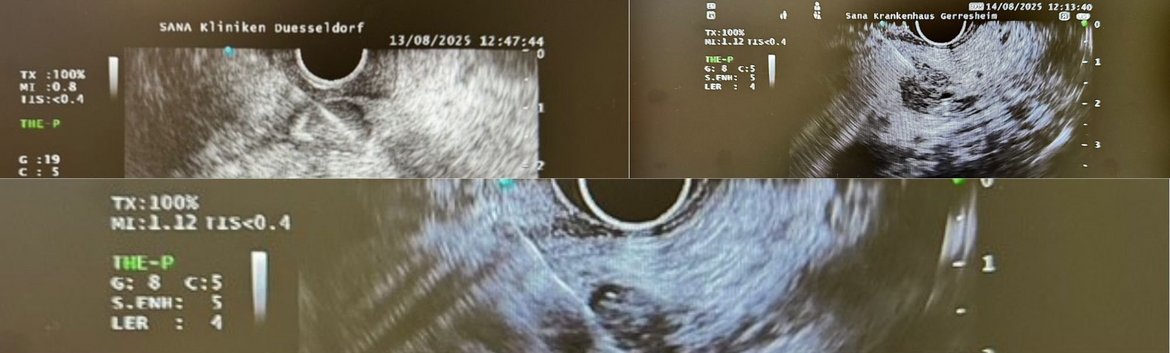

endosonographische FNP von unklaren Raumfoderungen im Pankreas

In der Diagnostik und Therapie von Pankreaserkrankungen hat die Endosonographie (EUS) einen festen Stellenwert. Dabei werden zwei verschiedene Schallköpfe eingesetzt, die an der Spitze des Endoskops eingebaut sind. Der radiäre Schallkopf liefert analog zur Computertomographie ein 360° Bild, während der lineare Schallkopf, ähnlich wie ein Abdomenschallkopf, ein konvexes Bild und die Möglichkeit der ultraschallgesteuerten Punktion ergibt. Beide Schallköpfe haben die Möglichkeit einer Duplex-/ Kontrastmittelsonographie sowie Elastographie, so dass sicher zwischen Gang- und Gefäßstrukturen, als auch zwischen benignen und malignen Formationen unterschieden werden kann.

Der größte Vorteil der Endosonographie im Vergleich zur Computertomographie (CT) und Magnetresonanztomographie (MRT) liegt in der durch die Ortsnähe bedingten hohen Auflösung und durch die Möglichkeit beliebig wiederholbarer Schnitte, womit auch Läsionen im Millimeterbereich sicher erkannt und eingeschätzt werden können. Ferner sind hierdurch komplikationsarme Gewebeproben von suspekten Strukturen während des Untersuchungsvorganges möglich. Die in der Durchführung sehr anspruchsvolle Methode wird überwiegend in gastroenterologischen Zentren eingesetzt – auch am Sana Standort Gerresheim. In differentialdiagnostisch schwierigen Fällen ergänzen sich die Methoden EUS, CT und MRT.